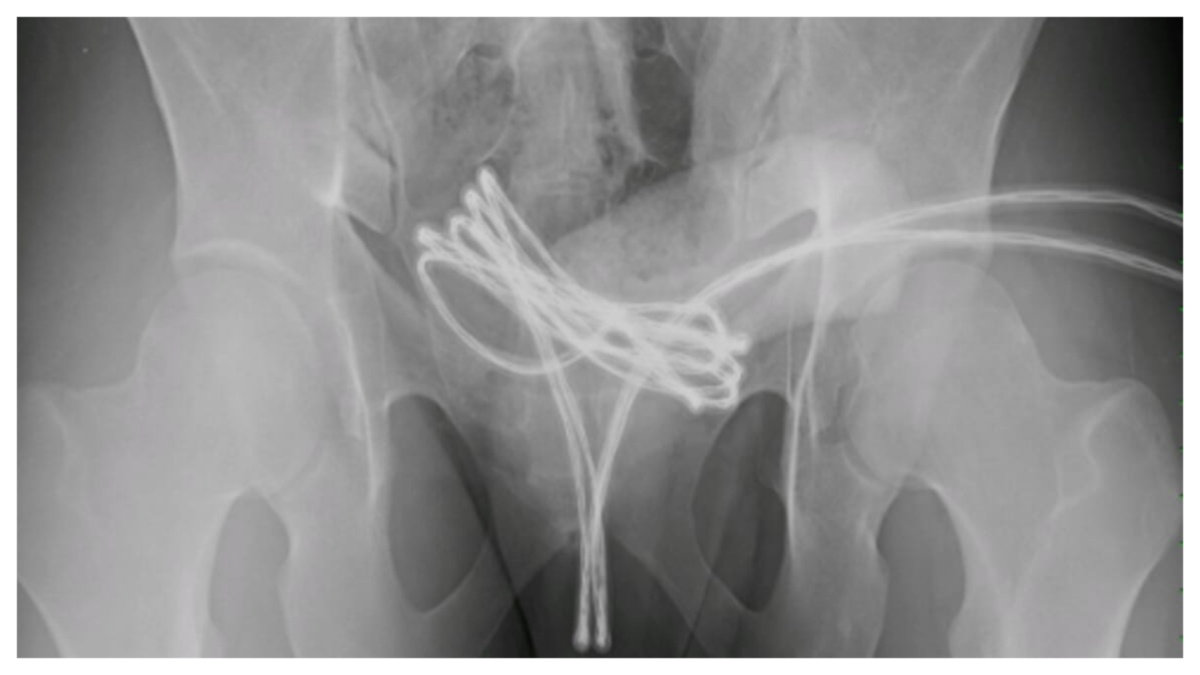

Un giovane britannico di 21 anni è stato costretto a ricorrere alle cure del pronto soccorso dopo aver introdotto un cavo USB nell’uretra. Lo studente universitario, il cui nome non è stato divulgato, aveva inserito il cavo nel canale urinario all’interno del pene, durante una pratica erotica rischiosa conosciuta come “sounding”. L’oggetto si è però bloccato. All’arrivo in ospedale, i sanitari si sono trovati davanti a una scena piuttosto inusuale: le estremità del cavo fuoriuscivano dall’orifizio uretrale, mentre il segmento centrale era completamente all’interno. Una radiografia dell’apparato urinario ha rivelato che il cavo, spinto in profondità e ripiegato su sé stesso, era arrivato fino alla vescica dove si era incastrato.

I medici hanno inizialmente tentato una rimozione manuale, senza successo. Hanno quindi proceduto ad anestetizzare il paziente e ad estrarre con cautela il cavo Usb utilizzando un ureteroscopio semirigido introdotto nell’uretra. Secondo quanto riportato dalla rivista “Cureus”, il giovane è rimasto ricoverato per sette giorni e poi è stato dimesso con una prescrizione di antidolorifici e antibiotici. Al controllo successivo, avvenuto un mese dopo, non sono emersi danni permanenti.